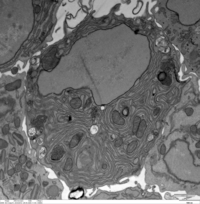

What happened to me? Can anyone help me?

CEACAM1-deficient BMDM was captured on day 0 after M-CSF treatment. The image was taken using a  transmission Electron Microscope.

-Anggi Muhtar Pratama